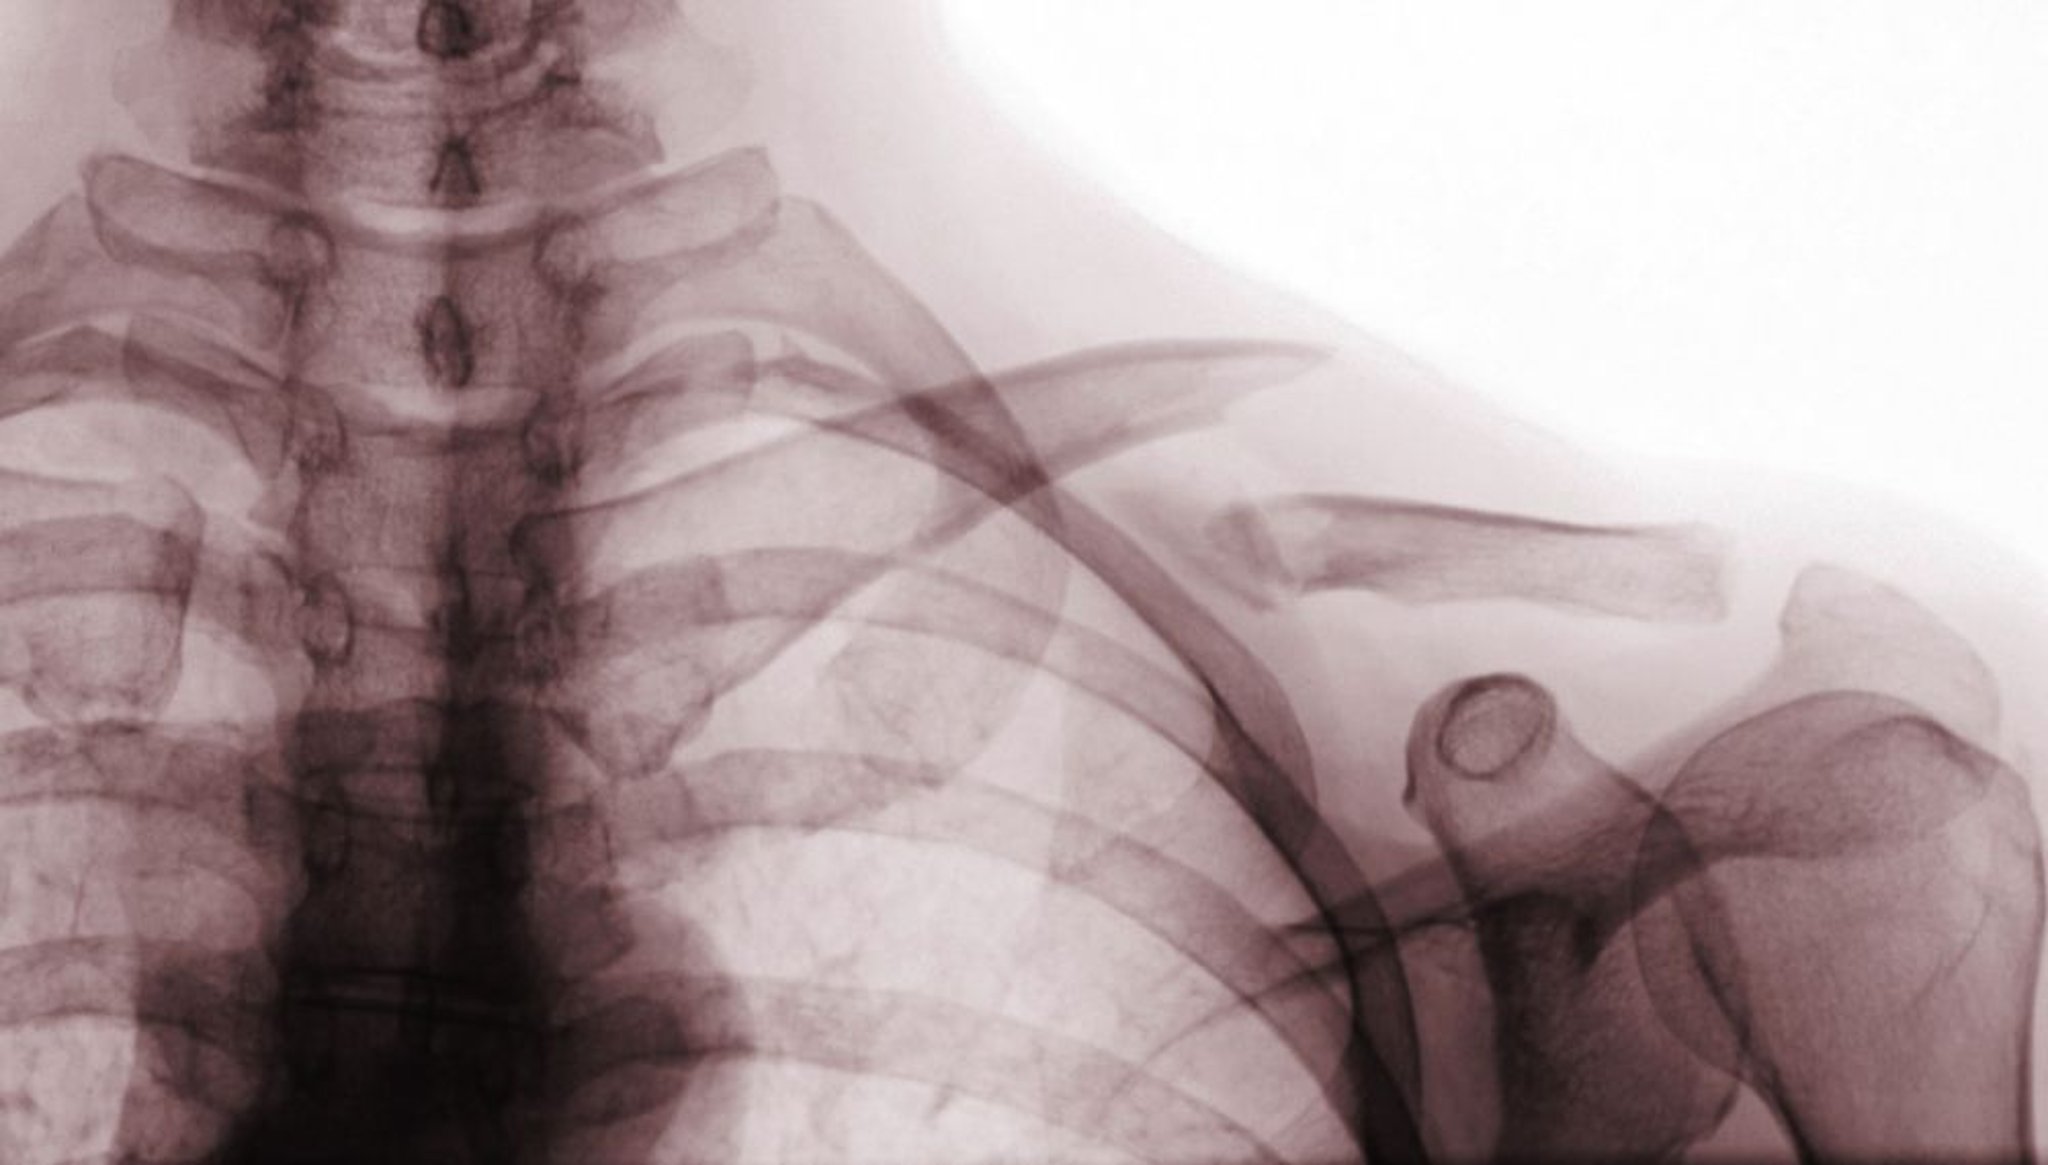

鎖骨骨折

このX線前後像には,鎖骨中3分の1の転位骨折(Class A骨折)が写っている。

Scott Camazine/SCIENCE PHOTO LIBRARY